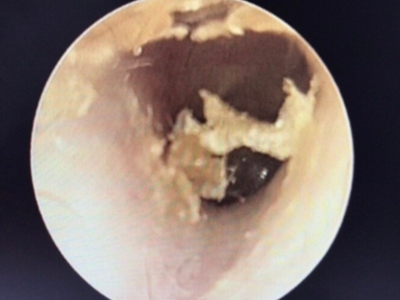

外耳道耵聍栓塞耳内有多个膜状物图

外耳道耵聍栓塞患者外耳道软骨部皮肤耵聍腺、皮脂腺不断分泌出黏性物质,均匀分布在外耳道处,干燥后形成黄白色鳞屑,并不断脱落。